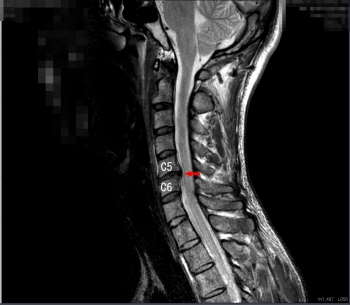

頚椎椎間板ヘルニア

神経の圧迫について

その椎間板の中身の髄核が飛び出て、頚椎の中の神経が圧迫されて、痛みやコリ、痺れなどが現れます。